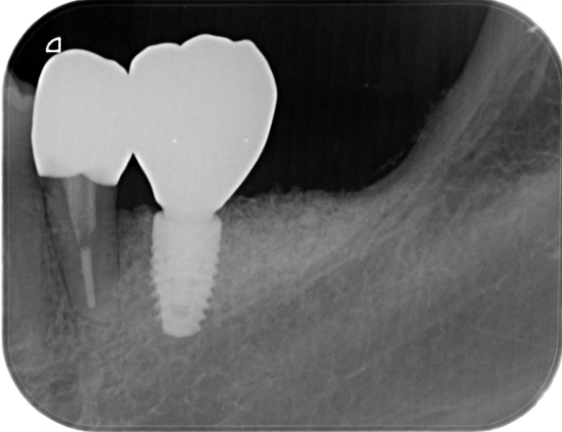

症例4

| 医院の診断 | 右下第二小臼歯の歯根破折 |

| 通院期間 | 1年 |

| 来院回数 | 16回 |

| 治療費 | 総額:1,940,000円(税抜) 【内訳】 インプラント埋入手術250,000円×2、GBR(骨再生手術)150,000円、2次手術+FGG(遊離歯肉移植術)55,000×2+80,000円、仮歯30,000円×2、インプラント上部構造(セラミッククラウン)170,000円×2、周囲歯のやりかえ:精密根管治療100,000円(大臼歯)+80,000円(小臼歯)、ファイバーポスト&コア(歯の補強)20,000円×2、セラミッククラウンのやりかえ120,000円×4 |

| リスクと副作用 | 定期的なメンテナンスが必要、術後若干の腫れと痛み |

| ここがこだわりのポイント!☝ | インプラント周囲に角化歯肉と言われる健常な歯肉がなかったので、口蓋からの歯肉移植を行っています💡 |